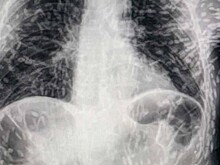

Ученые поделились рентгеном человека, тело которого было усеяно яйцами паразита

Новости

9 мая 2023